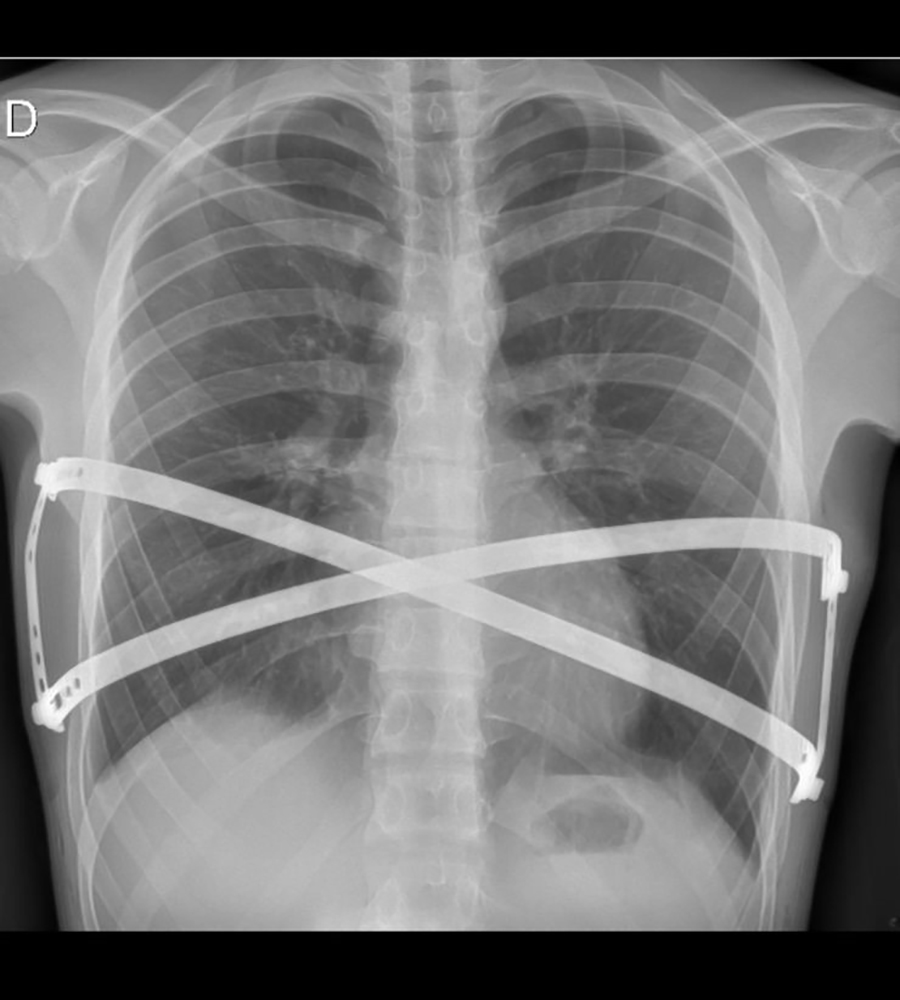

“Até o ano passado, o único material disponível para a cirurgia de Nuss, era importado e feito de aço, o que podia trazer complicações pelo deslocamento da barra metálica no corpo. Recentemente, uma fábrica brasileira começou a produzir a barra com titânio. Ela é curva e moldada conforme a deformidade de cada paciente, mas o titânio é um material sem contraindicações, já que é livre de níquel e de outros metais que podem provocar problemas no organismo, como alergias. O material é retirado após dois anos da cirurgia”, complementa Ogawa.

A cirurgia de Nuss, realizada no Hospital Marcelino Champagnat, durou cerca de quatro horas. O ineditismo do procedimento ficou por conta do material utilizado – titânio -, que praticamente elimina a possibilidade de deslocamento das barras metálicas e proporciona resultado anatômico de correção melhor.

“O aço foi trocado por titânio e o serrilhado que existia para ajustar o fio de aço passou a ser desnecessário, o que deve facilitar a retirada da barra. Outra novidade incorporada aqui no Brasil é a chamada técnica sanduíche: em vez de uma única barra de metal empurrando o esterno para fora, utilizamos duas. Uma fica embaixo e a outra por cima desse osso e ambas estão ligadas entre si, eliminando a possibilidade de deslocamento”, conta Tedde.